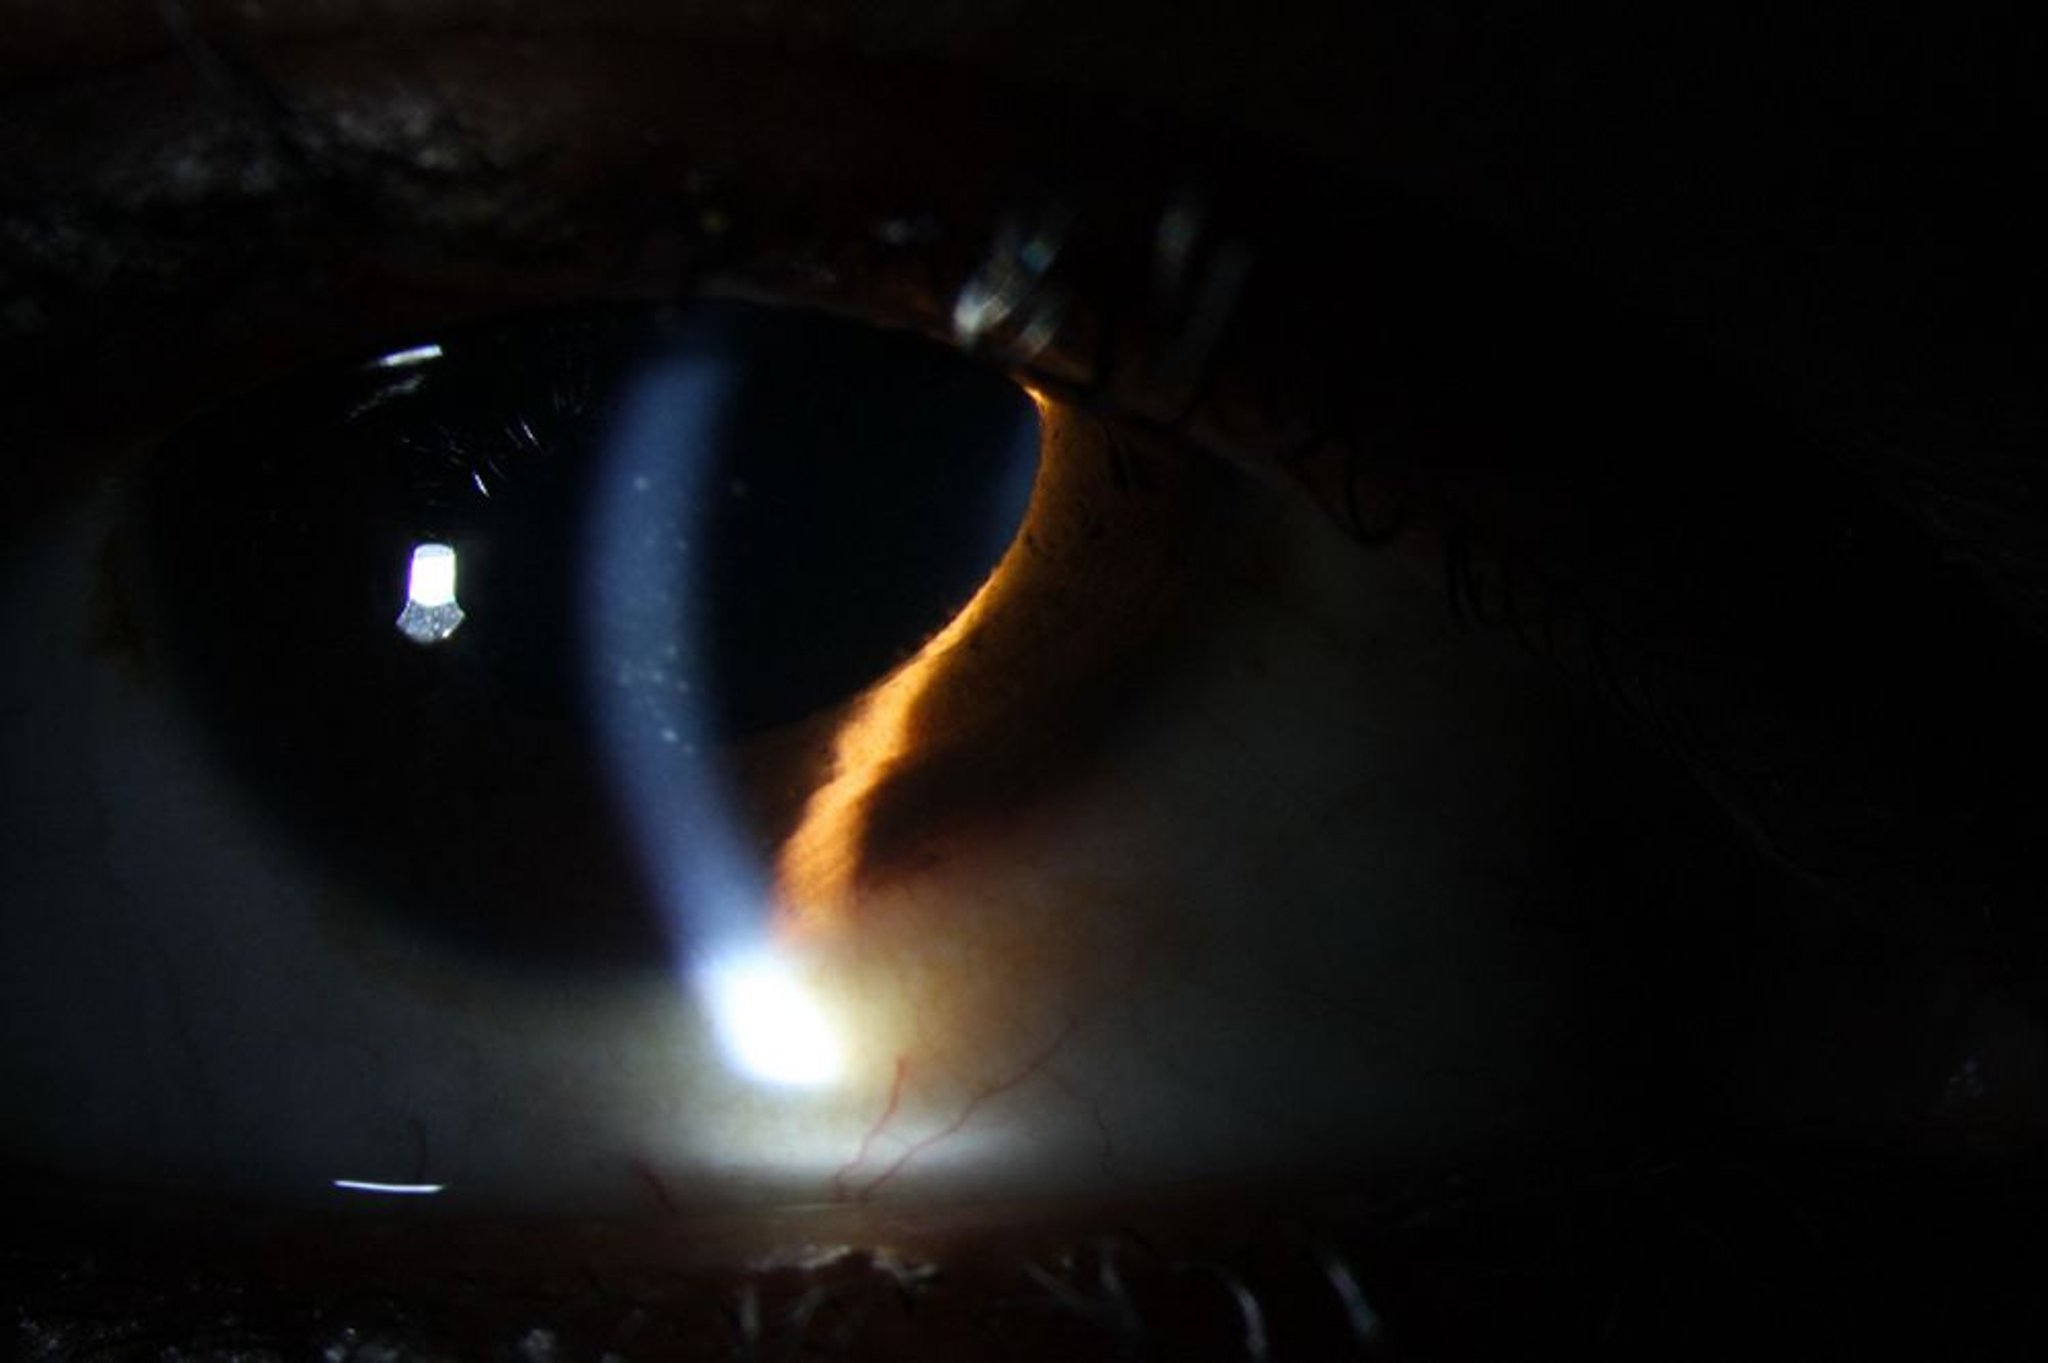

ぶどう膜炎(前部)

前部ぶどう膜炎では,充血,角膜内皮上の角膜後面沈着物,ならびに前房の白血球集簇およびフレア(タンパク質)を生じることがある。

Image courtesy of Sunir Garg, MD.